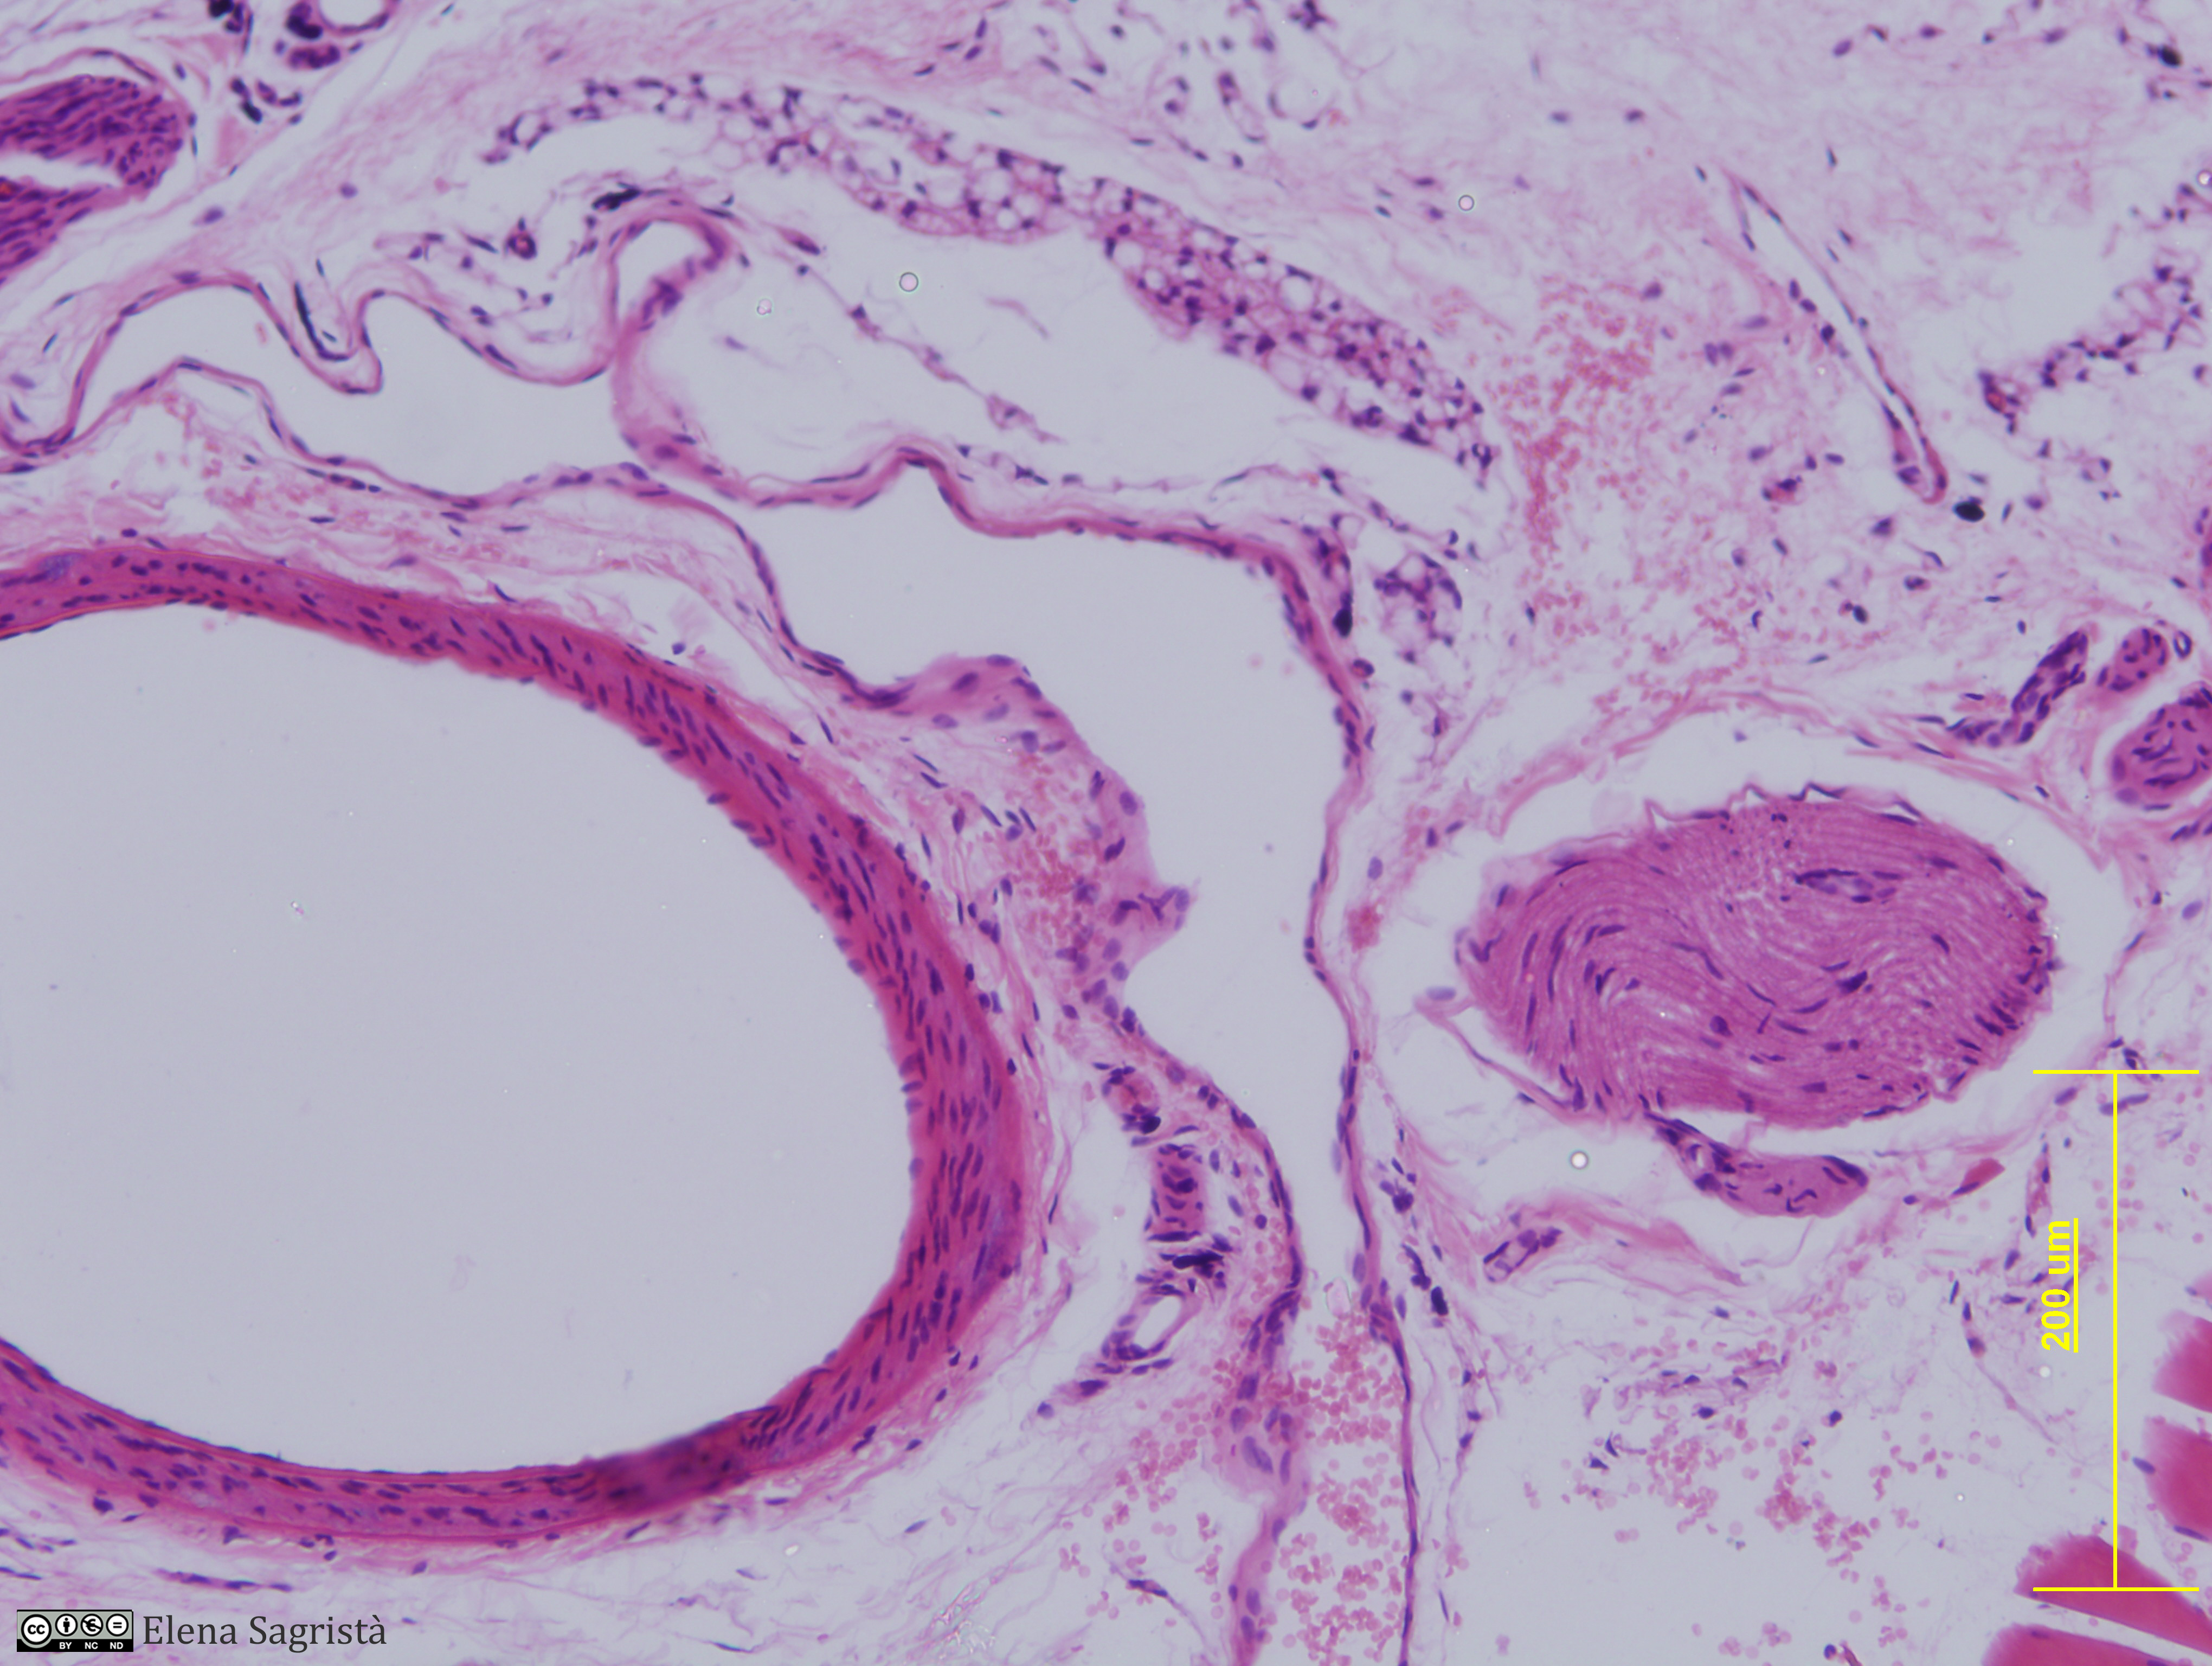

Histologia imatges: 10 Vasos sanguinis i limfàtics

Imatges de preparacions histològiques de Vasos sanguinis i limfàtics. Microscopia òptica.